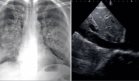

La ecocardiografía mostró un aneurisma del septo interauricular tipo 1R, con protrusión mayor a 10 mm hacia la aurícula derecha, junto con un quiste sanguíneo de 1.9 x 1.6 cm en el velo posterior de la válvula mitral. No se observó defecto septal, pero se detectó regurgitación mitral leve a moderada con función ventricular conservada.

Los estudios de laboratorio, incluidos proteína C reactiva, título de antiestreptolisina O (ASO) y marcadores serológicos para sífilis e infecciones retrovirales, resultaron negativos. La radiografía de tórax y el electrocardiograma fueron normales.

Ante la ausencia de criterios ecocardiográficos o serológicos para enfermedad reumática, se descartó el diagnóstico inicial y se estableció como diagnóstico definitivo aneurisma del septo auricular asociado a quiste valvular mitral.